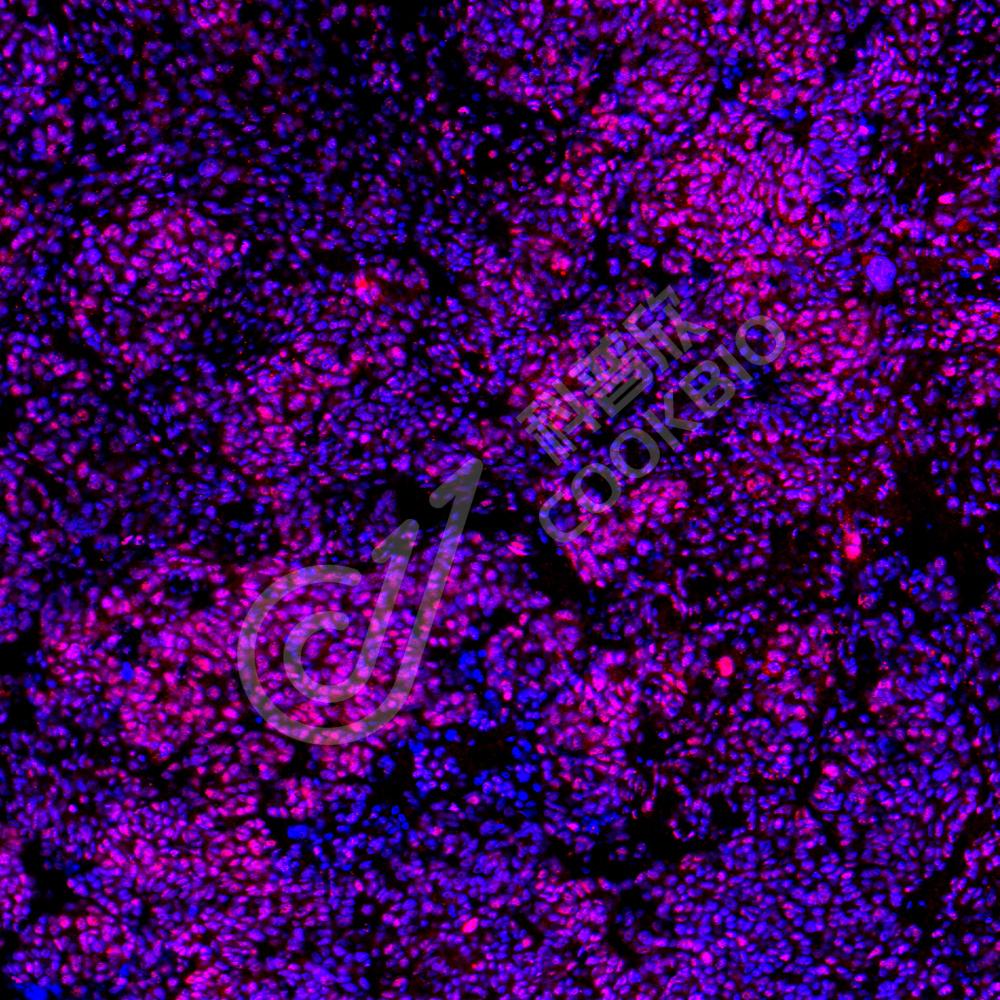

IF检测Y14蛋白(货号 K1335187)(红色).

样品: 人卵巢癌, 4%多聚甲醛 (货号KSG1101) 固定12-24小时.

抗原修复: Tris-EDTA抗原修复液(pH 9.0) (KSG1203), 98℃, 20分钟.

封闭: 3% BSA(货号KSGC305010)的PBS溶液, 室温孵育30分钟.

—抗: 1: 600稀释, 4℃ 孵育过夜.

二抗: Cy3标记山羊抗兔IgG (H+L) (货号KB63909), 1: 300稀释, 室温孵育1小时.